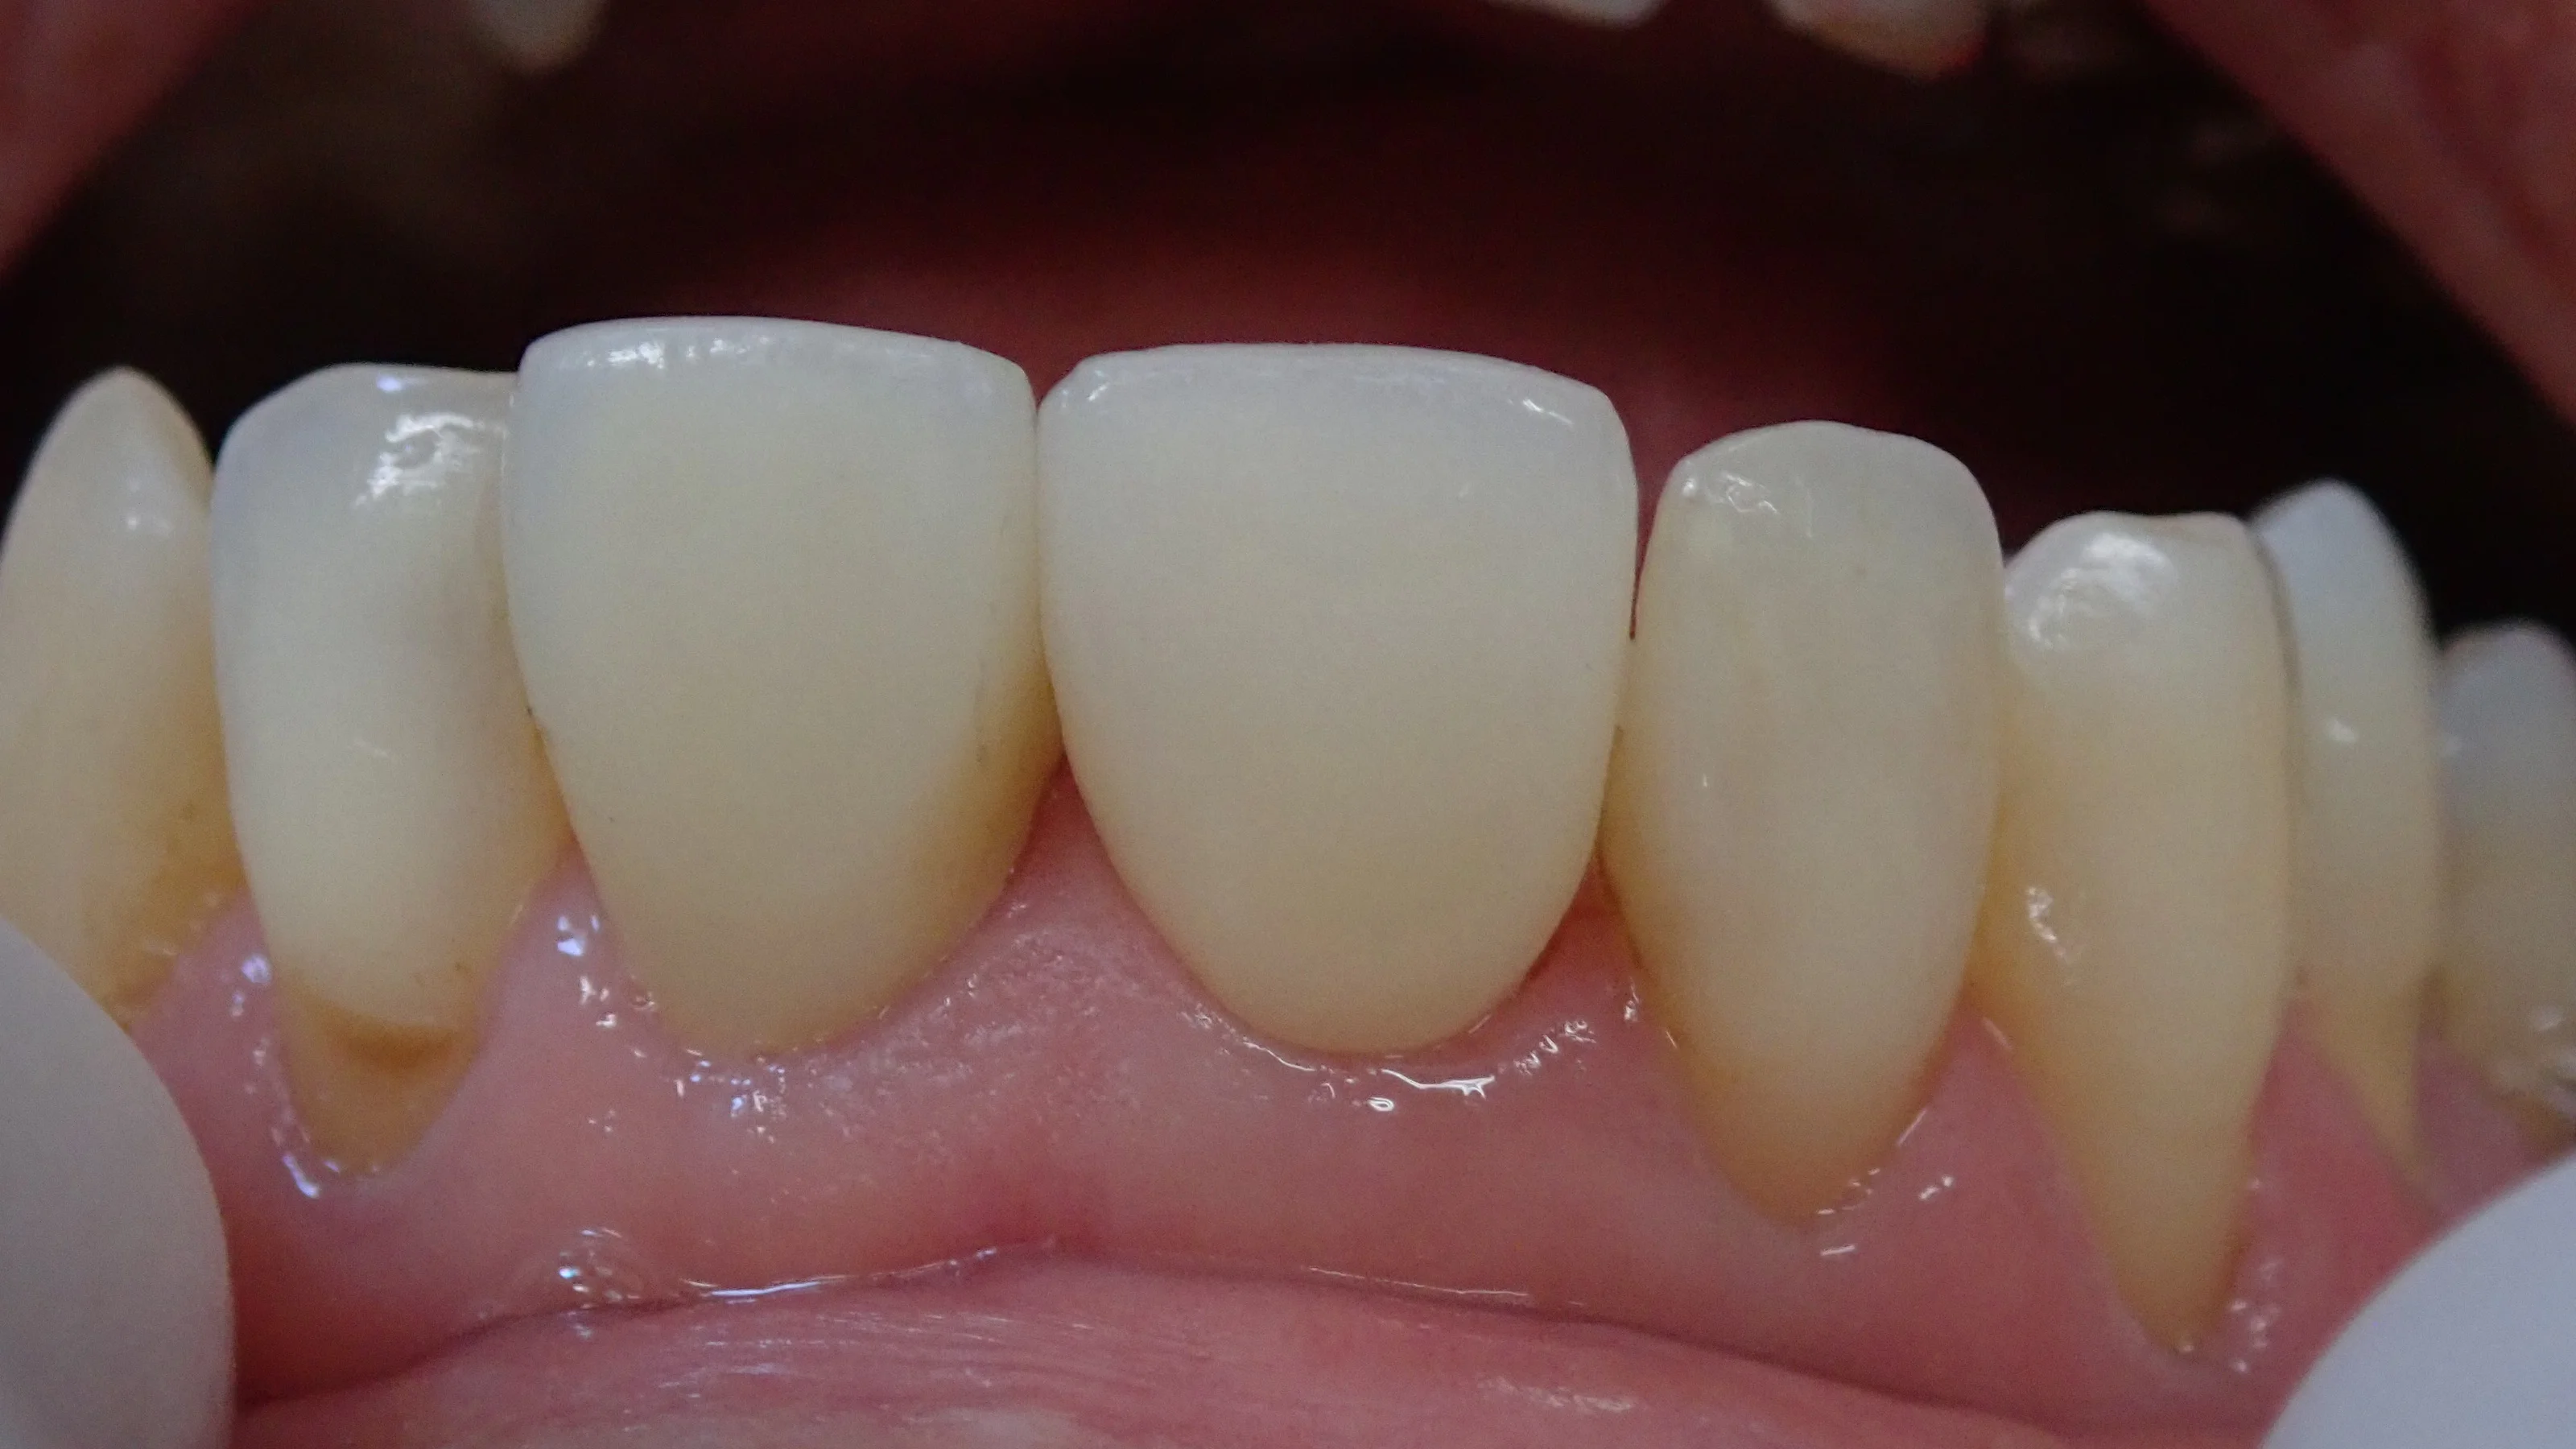

で、セラミックを接着した後の写真がこちら。

写真だと少し分かりづらいですが、根本1/5くらいの色が若干黄色っぽいんですよね。

技工士さんが上手く再現してくれたと思います。

ご本人も歯磨きを非常に綺麗に磨いていてくれていたので、炎症も全くなく、すっぽりと綺麗に入りましたね。